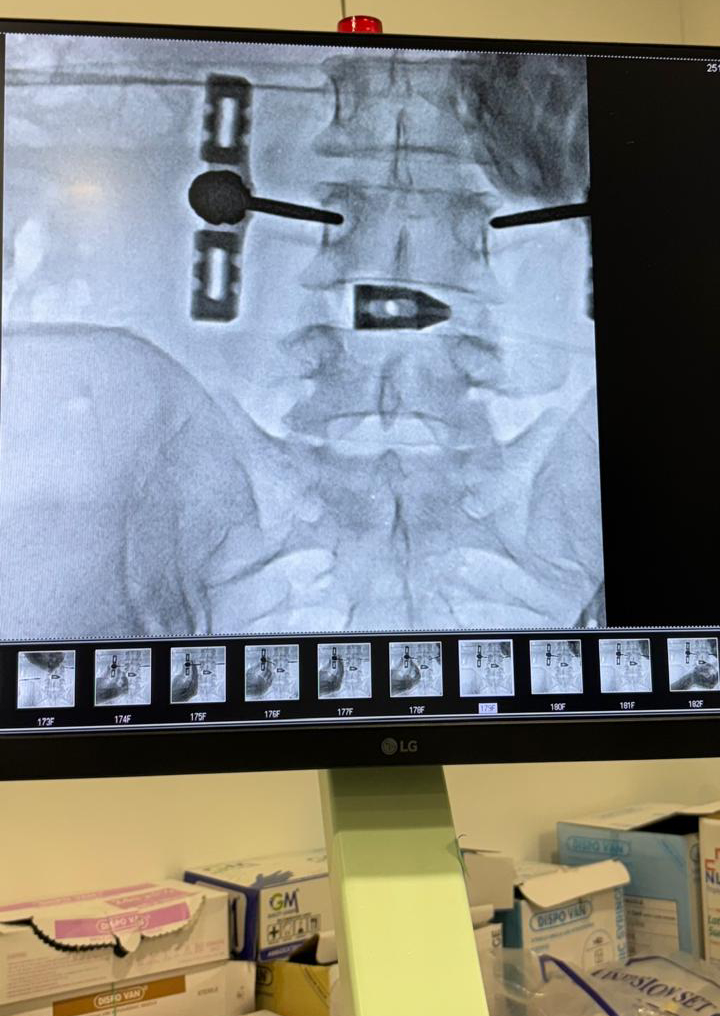

ભાવનગર ખાતે સૌ પ્રથમવાર અમેરીકા માં થતી એન્ડોસ્કોપિક (દૂરબીન વડે) મણકા ની OLLIF સર્જરી સફળતાપૂર્વક કરવામાં આવી.

ભાવનગર પેઈન એન્ડ સ્પાઇન સેન્ટર ખાતે OLLIF – ઓબ્લિક લેટરલ લમ્બર ઇન્ટરબોડી ફ્યુઝન-એન્ડોસ્કોપિક (દૂરબીન વડે) સ્પાઇન ફિક્સેશન માટે અતિ આધુનિક સારવાર કરાઇ. આ અદ્યતન ટેકનોલોજી કે જે અમેરિકા જેવા દેશો માં થતી સારવાર છે અને એન્ડોસ્કોપિક ફ્યુઝન સ્પાઇન સર્જરિ તરીકે ઓળખાય છે. આ સારવાર માં આખા મણકા ખોલ્યા વગર માત્ર દૂરબીન વડે જ ફિક્સેશન કરવામાં આવે છે જેનાથી ઓછા માં ઓછો ચેકો, લોહી નું નહિવત નુકસાન, દર્દી નો દાખલ રહેવા નો સમય ખૂબ જ ઓછો, માસ પેશી ઓ ને ઓછા માં ઓછું નુકસાન તેમજ સારવાર બાદ નહિવત દુખાવો જેવા ફાયદા છે.ભાવનગર પેઈન એન્ડ સ્પાઇન સેન્ટર એ શહેર ની સૌ પ્રથમ સુપરસ્પેશિયાલીટી પેઈન એન્ડ સ્પાઇન હોસ્પિટલ છે જ્યાં તમામ દુખાવા ની સારવાર મિનિમલ ઇન્વેસિવ (કાપકૂપ વગર) પદ્ધતિ થી કરવામાં આવેલ છે. ઓલિફ-OLLIF સારવાર ઝાયડસ હોસ્પિટલ ના ખ્યાતનામ તબીબ ડૉ. યક્ષ સોમપુરા (દૂરબીન સારવાર ના નિષ્ણાંત ) તેમજ ડો. હેતલ લીંબાણી (પેઇન અને સ્પાઇન ફિઝિશિયન) ના સહિયારા પ્રયાસો થી સફળતા પૂર્વક કરવામાં આવી .